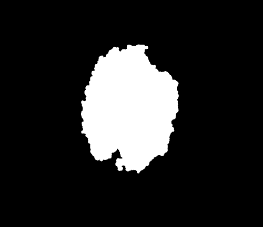

Skin lesion segmentation is one of the crucial steps for an efficient non-invasive computer-aided early diagnosis of melanoma. This paper investigates how color information, besides saliency, can be used to determine the pigmented lesion region automatically. Unlike most existing segmentation methods using only the saliency in order to discriminate against the skin lesion from the surrounding regions, we propose a novel method employing a binarization process coupled with new perceptual criteria, inspired by the human visual perception, related to the properties of saliency and color of the input image data distribution. As a means of refining the accuracy of the proposed method, the segmentation step is preceded by a pre-processing aimed at reducing the computation burden, removing artifacts, and improving contrast. We have assessed the method on two public databases, including 1497 dermoscopic images. We have also compared its performance with classical and recent saliency-based methods designed explicitly for dermoscopic images. The qualitative and quantitative evaluation indicates that the proposed method is promising since it produces an accurate skin lesion segmentation and performs satisfactorily compared to other existing saliency-based segmentation methods.